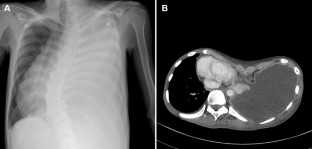

A 27-year-old man with severe pectus excavatum, dextrocardia and spinal scoliosis underwent thoracoscopic pleural decortication due to failure of 1-month medical treatment for tuberculous empyema. One month after the pleural decortication, he again underwent open thoracostomy window for repetitive pleuro-cutaneous fistula with tuberculosis empyema. He was subsequently referred to our clinic for progressive dyspnea and bilateral leg edema 4 months after the open thoracostomy window. Evaluations revealed deterioration of the chest wall depression and further compression of the inferior vena cava, which were considered an aggravation of the pectus excavatum after the open thoracostomy window. Herein, we present an extremely rare case of deterioration of chest wall depression causing congestive hepatopathy after an open thoracostomy window in a patient with pectus excavatum and tuberculosis empyema.

Fig. 1